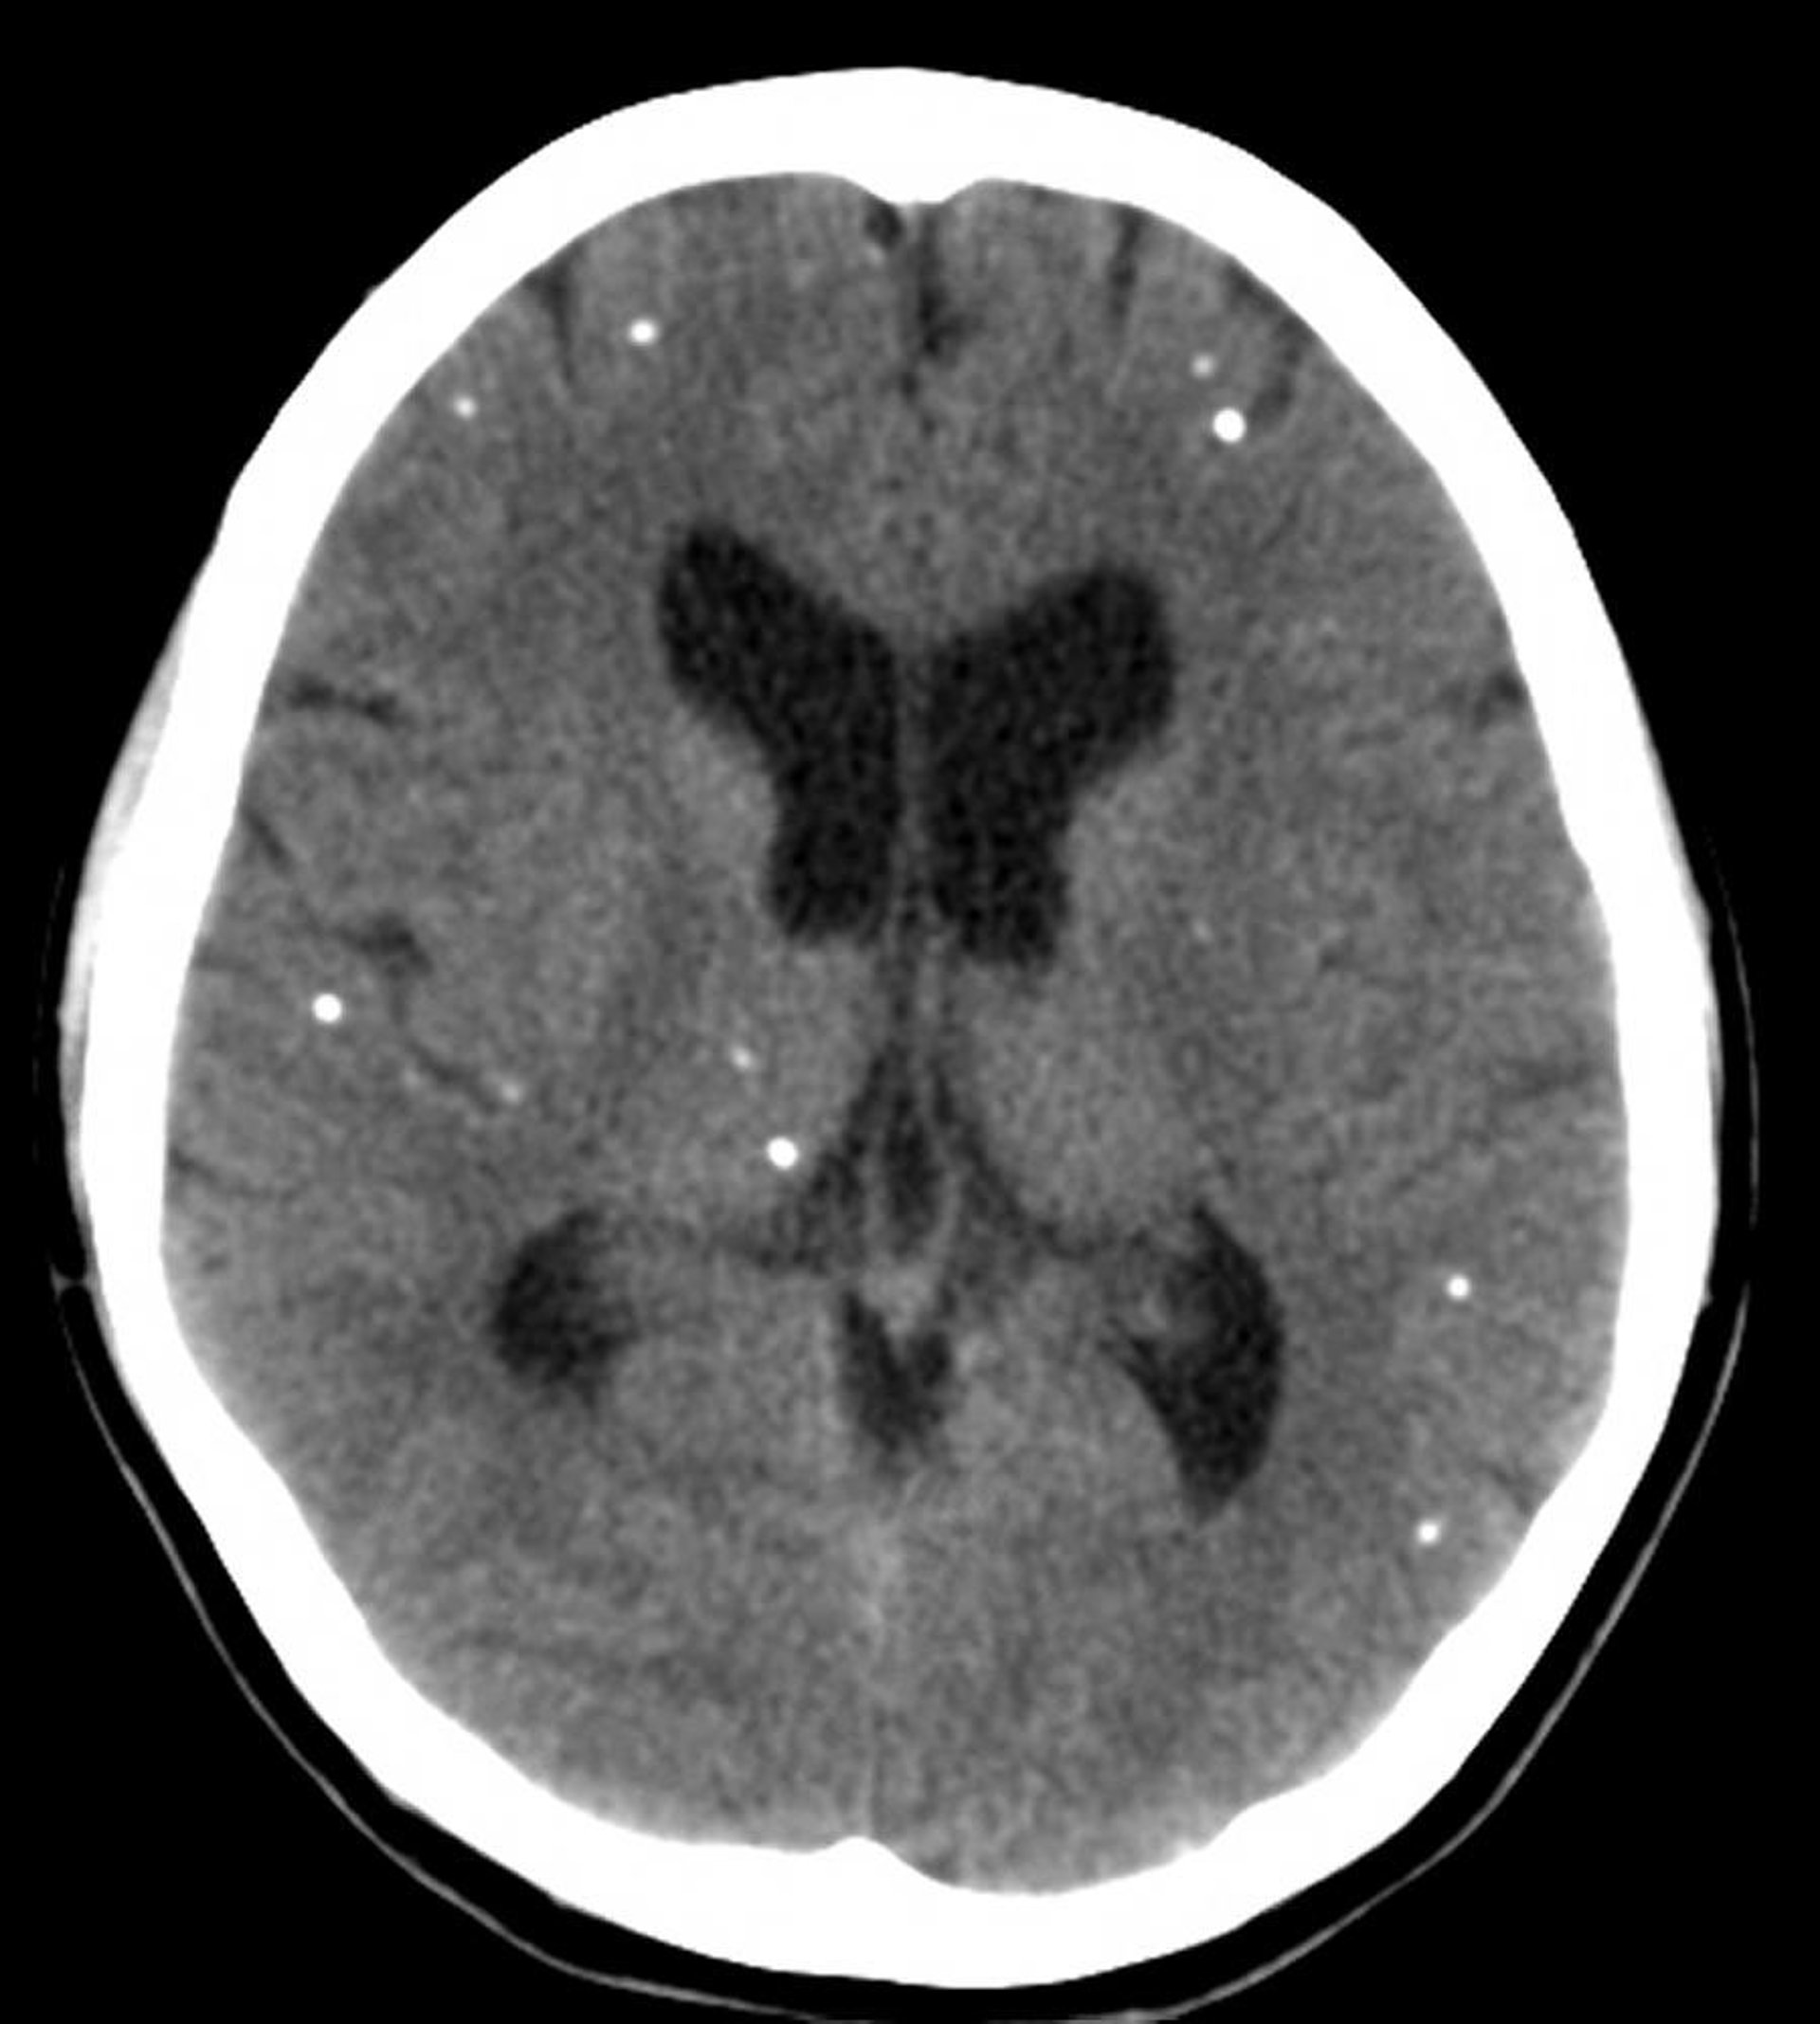

La neurocisticercosi è da sospettare in quei pazienti che vivono o che provengono da paesi in via di sviluppo e che hanno meningite eosinofila o crisi epilettiche inspiegabili, deficit cognitivi o focali o cambiamenti della personalità. La diagnosi viene suggerita dalle molteplici lesioni cistiche calcificate osservate con la TC o la RM; il mezzo di contrasto può essere utile per evidenziare le lesioni. La diagnosi richiede test sierologici e liquorali e occasionalmente la biopsia della cisti.

Questa scansione TC mostra aree multifocali di calcificazione che rappresentano cisti calcificate in un paziente con neurocisticercosi.

Courtesy of John E. Greenlee, MD.